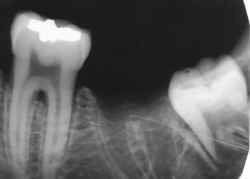

Identificação Humana por Comparação Computadorizada de Imagens

Radiográficas Dentárias